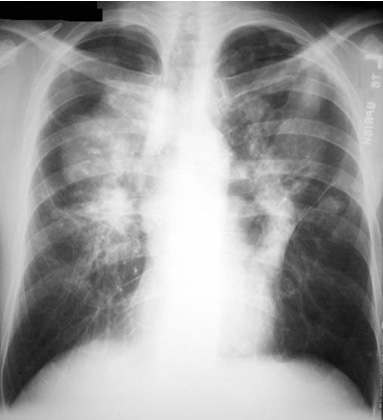

Sarcoidosis

Progressive massive fibrosis

Bilateral upper lobe diseae.

Conglomeration of mass and fibrotic process.

Closely resembles Silicosis.